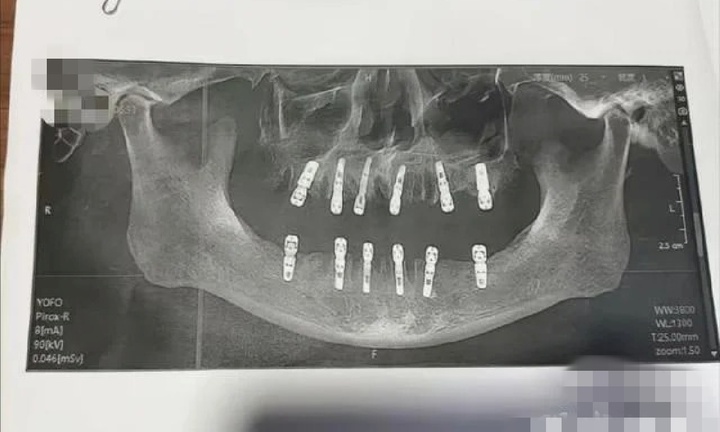

Theo thống kê từ các bệnh viện tuyến trung ương, tỷ lệ người gầy bị gan nhiễm mỡ không hề nhỏ. Ảnh minh họa.